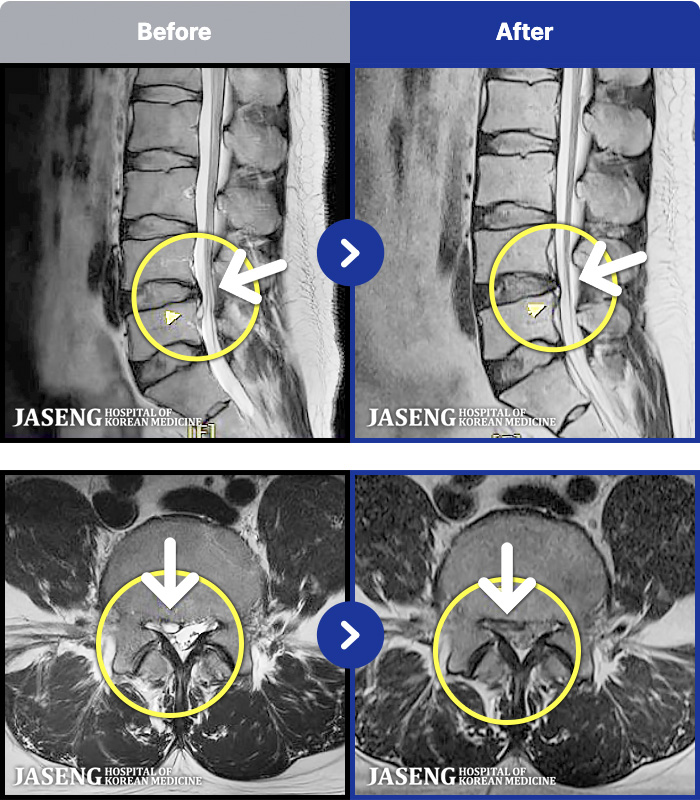

- MRI ġ

97 MRI ũ ʸ Ȯϼ.

[_㸮ũ] 㸮 , ٸ ȭǾ ϼ̽ϴ.